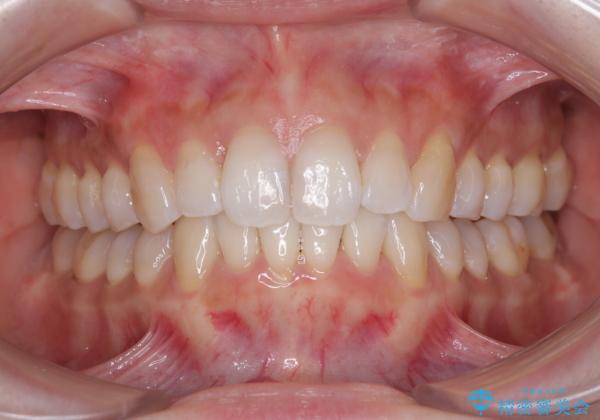

補助装置を用いて奥歯の咬み合わせを事前に改善 インビザラインによる矯正治療

歯列としてはインビザラインでもワイヤー矯正でも対応できるものでしたが、奥歯の咬み合わせを見た時に上顎がやや前方にあり、インビザライン単独では時間のかかってしまう可能性があるため、補助装置を治療当初に使用することで、インビザラインによる治療をスムーズに行えるように計画しました。

インビザラインは得意・不得意の差がはっきりとしているため、補助装置やワイヤー装置などをうまく活用することで、治療期間を短縮するとともに、より理想的な仕上がりを達成することができます。